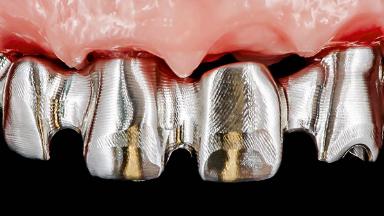

This case features the flapless computer-guided placement of 7 bone-level implants, distributed to provide maximal support for the prosthetic framework. A rigid one-piece metallic framework was utilized as an interim restoration to reduce the risk of fracture associated with this prosthetic design. As part of the clinical examination, the SAC Assessment Tool was used, resulting in a surgical and restorative risk classification as “complex”.